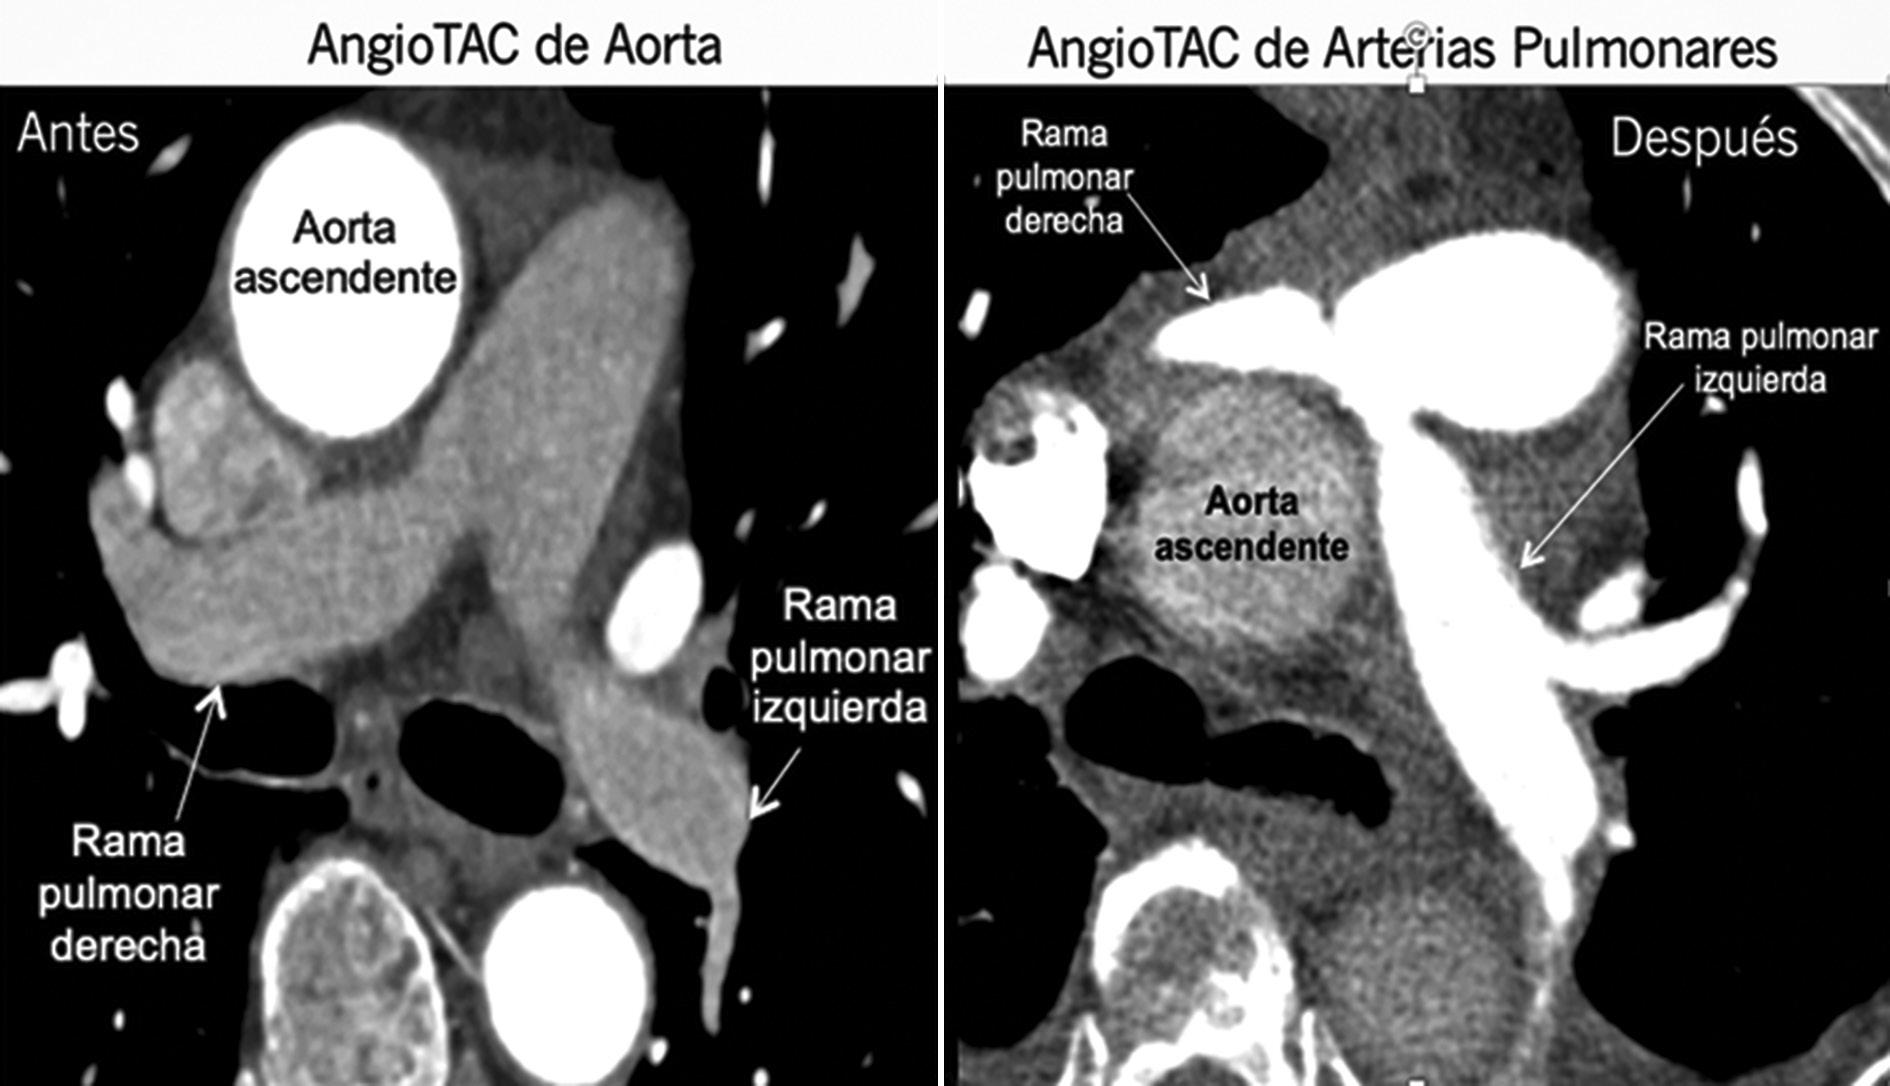

Presentamos el caso de paciente con dolor torácico secundario a un OAAC de la CI con curso interarterial donde se decidió destecho de la AC y la translocación de la arteria pulmonar (Lecompte) que permitió la resolución de sus síntomas (Fig. 2).

Figura 2 Comparación de Angio TAC de aorta con Angio TAC de arterias pulmonares, antes y después de la cirugía donde se aprecia el cambio en la implantación de la rama derecha de la arteria pulmonar, quedando ahora con curso anterior a la aorta.

El caso presentado representa un reto al clínico, al ser una patología poco común y por falta de estudios robustos se hace difícil sospecharla, diagnosticarla y tomar decisiones terapéuticas; en nuestro caso la decisión quirúrgica fue tomada en una junta multidisciplinaria compuesta por cardiólogos clínicos, cirujanos cardiovasculares y expertos en imágenes cardiacas. La edad del paciente y tener una prueba de inducción de isquemia negativa generó controversia sobre la necesidad de intervenir, sin embargo, se conoce que las pruebas de estrés pueden tener falsos positivos y negativos en estos pacientes, una prueba de estrés negativa no puede verse como tranquilizadora, especialmente cuando hay otros hallazgos anatómicos de alto riesgo o el paciente tiene síntomas1,5. El hecho de tratarse de un curso interarterial «maligno» de la CI considerado por sí mismo como una de las principales características de más alto riesgo de muerte súbita, además de la estrechez documentada en angiografía coronaria por tomografía computarizada en el curso interarterial y que los síntomas del paciente no pudieron explicarse de otra manera fueron la justificación para la decisión quirúrgica, luego de discutir riesgos y beneficios con el paciente.